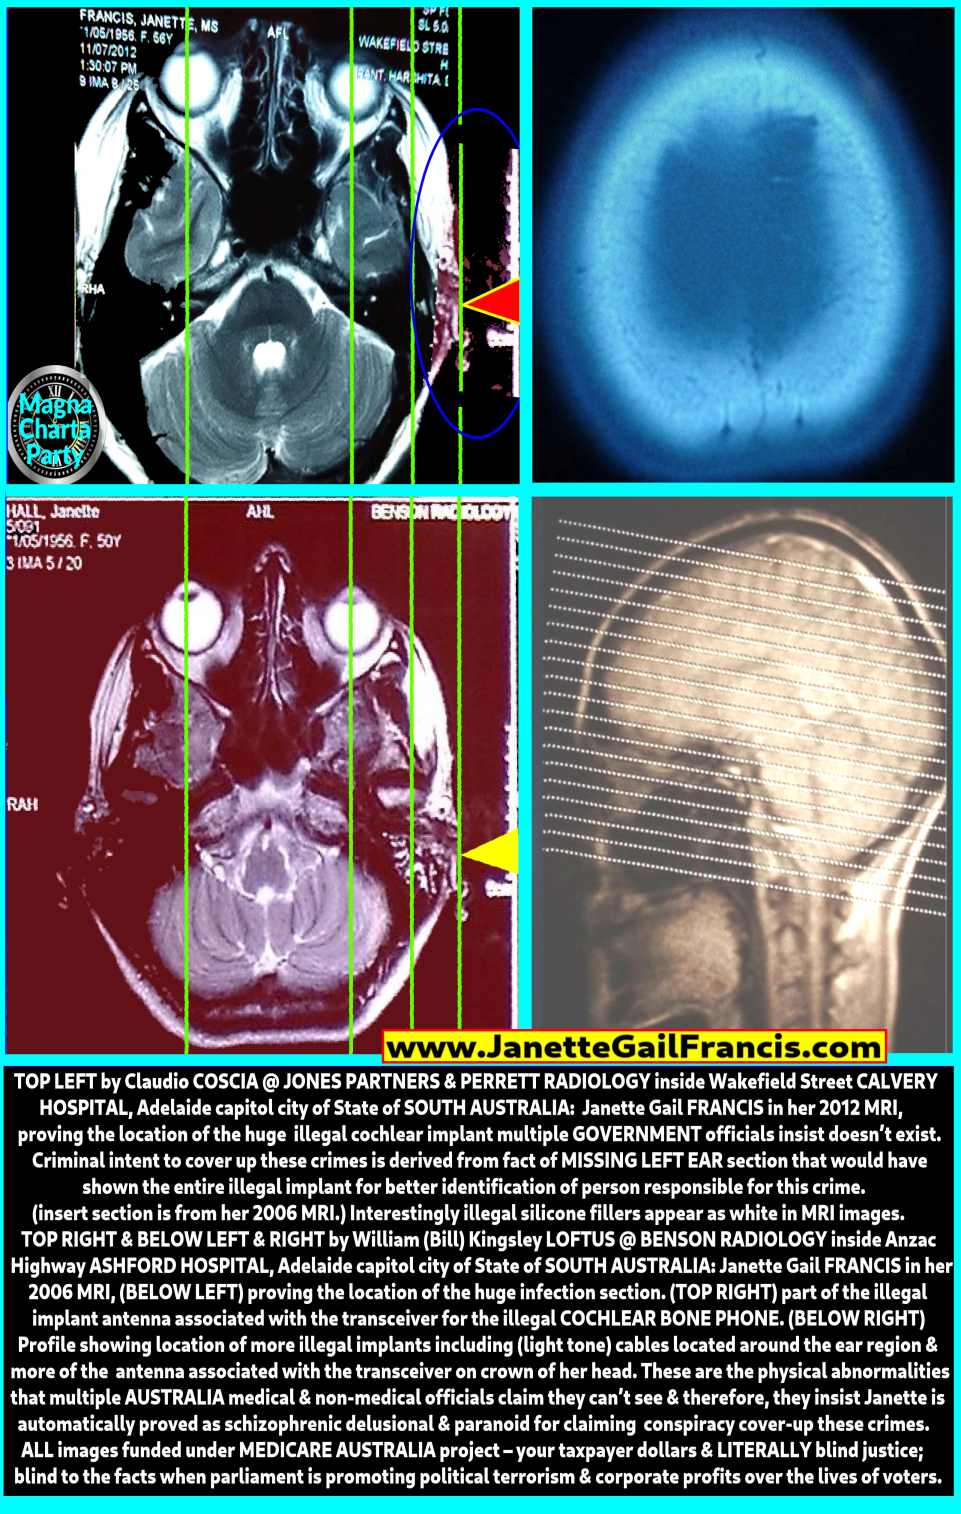

Very briefly: Because I witnessed serious crime on 24 April 1988, I was medically mutilated in greater western Sydney NSW as a desperate attempt to kill me when other direct attempts failed. I came to Adelaide in 2004, to get evidence and have the medical mutilations corrected but have been met with strong opposition in the form of supporters of the NSW assailants employed within the health department, the police department, the (public) housing department, transport department, and blocked in my access to civil court services to resolve the issues which are now compounded due to the passage of time. Since 1989 this family of psychopathically and sycophantically fixated and narcissistic Freemason fanatics as Australian, UK, USA, and NZ parliament supported political extremists have published the four (4) below false and misleading paperbacks to nullify me as a witness against Freemason meetings ritualistic and family child rape, child murder and Freemason's police officer assassinations (plural). One was funded by New South Wales State and Australian Federal parliaments to convert the terrorist lies into a television miniseries aired (in part or full) by Australia's Network 10 and Network 9 television stations as terrorist accomplices.

My website www.JanetteGailFrancis.com (www.WitchHunted.com) proves that since 2018 South Australia's government have illegally blocked my irrevocable statutory right to have my State drivers licence issued because (in writing to South Australia's police) I asked police to investigate medical crimes in the Adelaide to Onkaparinga local council regions of South Australia - and South Australia's police refuse to impose penalty against the offenders for perverting the course of justice and due administration of law because Australia is a terrorist nation.